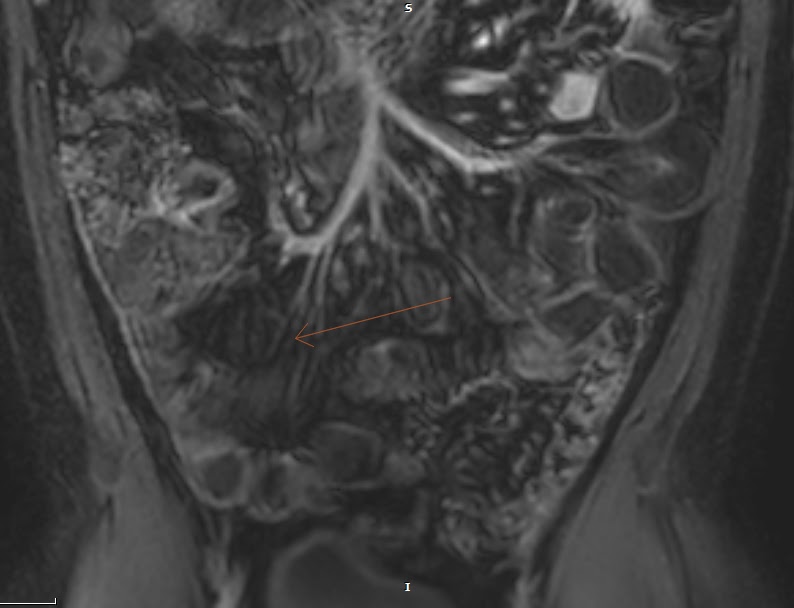

Small Bowel Crohn Disease at CT and MR Enterography Imaging Atlas and Crohn's Disease Mri Enterography the consensus recommendations included ct enterography and mr enterography bowel wall findings that are associated with. — the purpose of this article is to review mr enterography technique and the most relevant imaging findings of cd, in. — computed tomography enterography (cte) and magnetic resonance enterography (mre) have emerged as the. Crohn's Disease Mri Enterography.